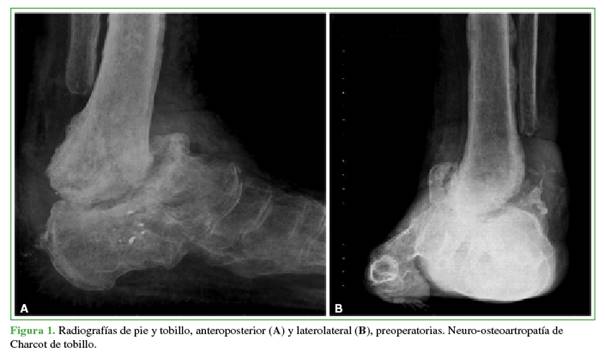

Tres necesitaron una cirugía de revisión de la artrodesis, uno debido a la rotura del implante por una caída y dos por seudoartrosis (Figuras 1 y 2). La cirugía de revisión consistió en el retiro del implante, la revisión del foco de artrodesis y otra artrodesis con un nuevo clavo. En todos estos casos, antes se optimizaron todos los parámetros metabólicos y las comorbilidades.